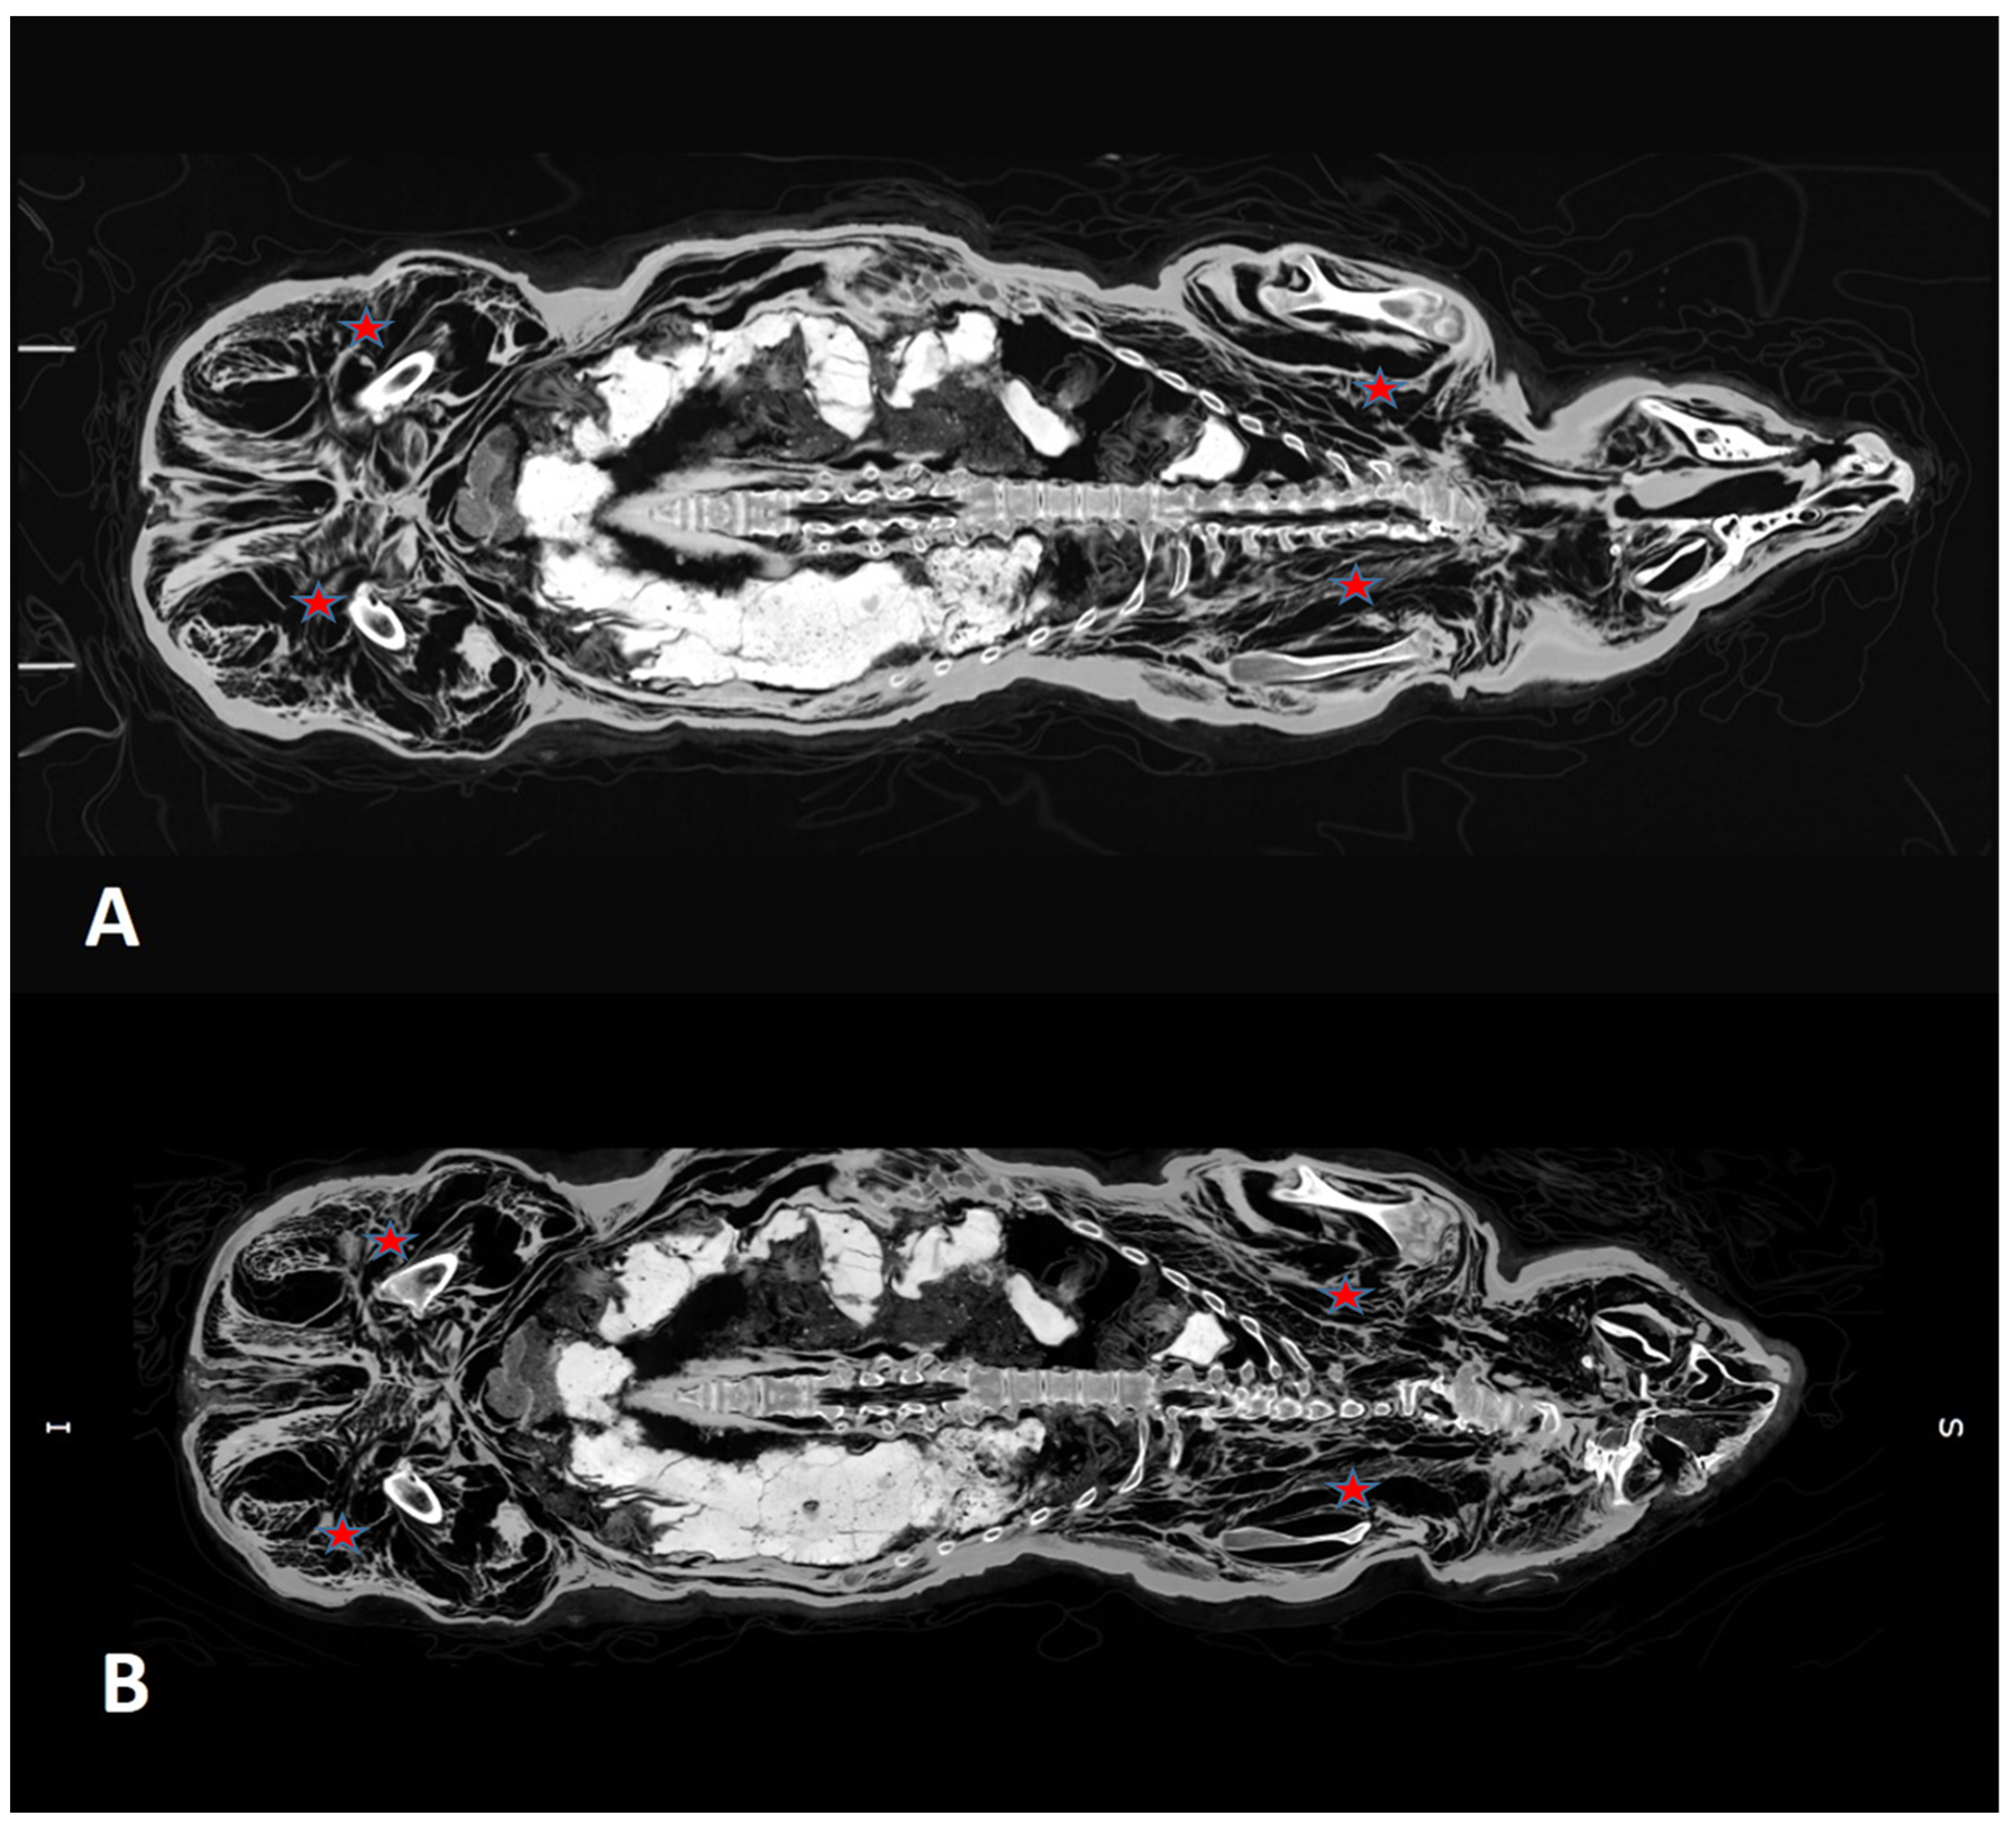

3.2. CT Scans After 7 and 13 Years